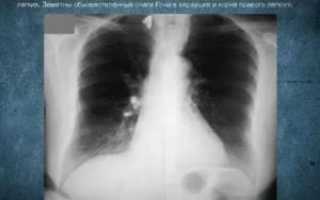

В повседневной жизни человек неоднократно сталкивается с возбудителем туберкулеза легких, даже не замечая этого. Подтверждением этому являются «случайные» находки при прохождении ежегодной плановой флюорографии, которые представляют собой очаги Гона. Как они формируются и несут ли опасность для организма, рассмотрим в этой статье.

Очаг Гона в легких является результатом первичного инфицирования человека микобактерией туберкулеза. Длительность его формирования в среднем составляет до 3 лет. Очаг Гона представляет собой овальное образование, иногда с неровными лучистыми контурами. Структура его представлена соединительной тканью, коллагеновыми волокнами, отложениями кальция. Размеры могут достигать 2 см.

При рентгенологических исследованиях очаг Гона представляет собой затемнение овальной (реже округлой) формы с резкими очертаниями, размерами до 5 мм. Образования могут быть единичными и множественными. Излюбленная их локализация – нижние и средние отделы легких. Иногда контуры очага могут быть неровные. Легочный рисунок неизменен, корень не расширен.